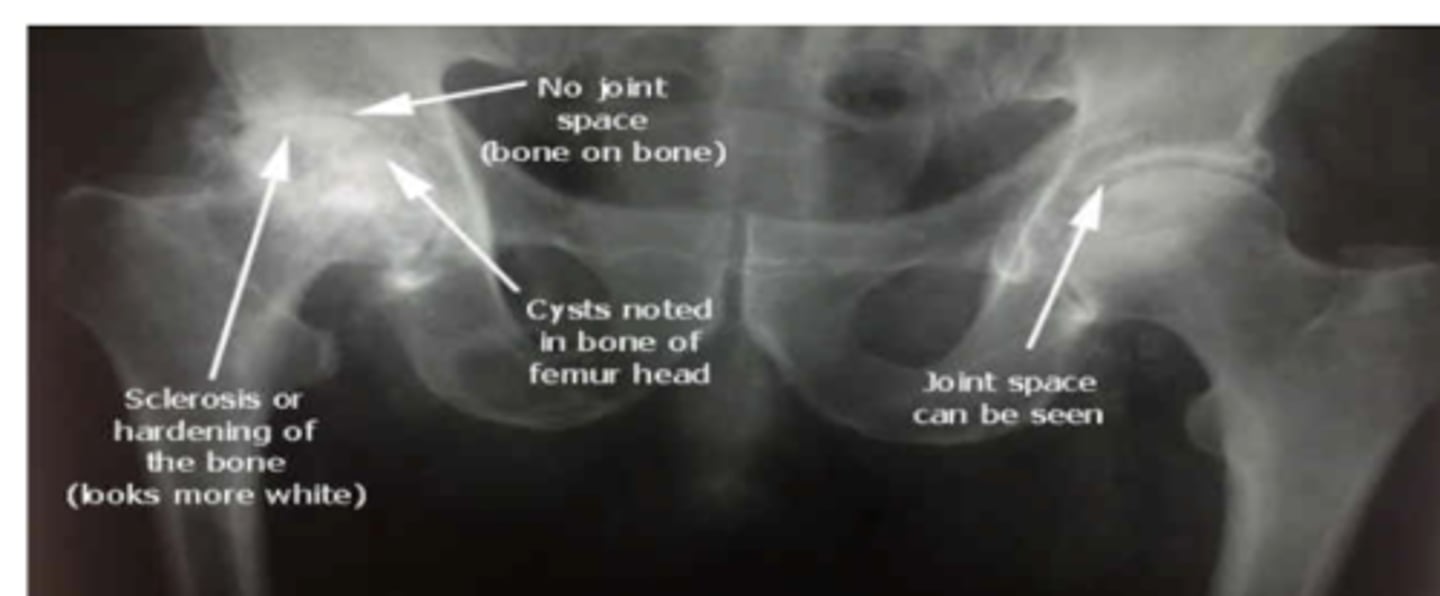

hip dysplasia on the Left photo

the L hip is worse than the R hip

very acute center edge angle

Hip OA